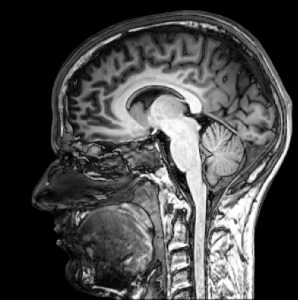

I made an appointment, and the doctor sent me to the neurologist. And now I remember that I had been worried about test results before. I’d been to this particular neurologist a couple of years ago with a persistent migraine, and I have to say I was worried about the results of the MRI scan then (it was nothing, and I haven’t had a migraine since).

MRI ScanThe neurologist’s clinic is walking distance away, and all the way there I was telling myself that although the result will be, as always, inconclusive, that I should prepare myself for some bad news. Just in case. Be prepared, I told myself, to find out you have motor neurone disease.